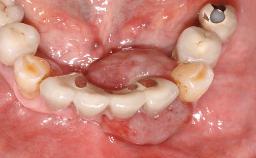

The patient presented with root fracture of the right central incisor with associated distal bone loss. After sectioning and extraction of the fractured root the distal papilla was lost, creating an esthetic compromise. This case demonstrates an option for treating this esthetic compromise. Early (Type 2) implant placement was performed at 7 weeks with simultaneous horizontal and vertical augmentation using Bio-Oss and Bio-Gide (Geistlich). After 3 months a connective tissue graft was performed at the time of implant exposure. Despite these surgical procedures, the papilla could not be recovered. As a result, a prosthetic solution was necessary.

Soft Tissue Contour and Volume Significantly deficient